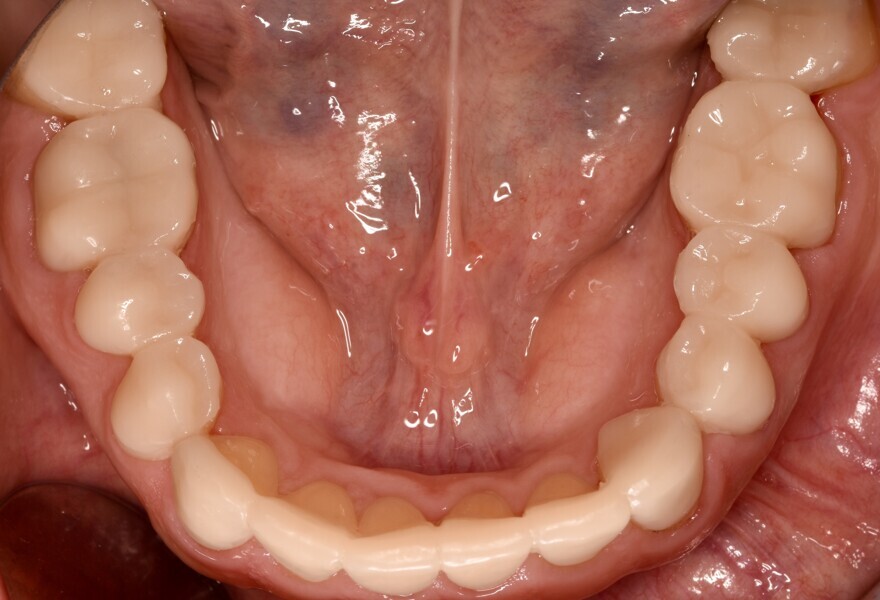

After a dripping time of 10 minutes, unpolymerised resin residue was removed from the printed objects using a brush soaked in isopropanol. The objects were then detached from the build plate, and the supporting structures were removed. Post-polymerisation was performed 15 minutes after the last isopropanol contact, using two cycles of 2,000 flashes each in the Otoflash G171 (NK Optik). After post-processing, the provisional restorations were finished and polished to a high gloss (Figs. 10a-g). Finally, the temporary luting was completed with a dual-polymerising temporary luting composite (Bifix Temp, VOCO; Figs. 11a-e).

After the provisional restorations had been worn for six months, the newly defined occlusal relationship was transferred to final restorations. Adhesively fixed restorations made of monolithic lithium disilicate (IPS e.max Press, Ivoclar) were the first choice (Figs. 12 & 13). Owing to the thin margins in some areas, it was preferable for the restorations to be fabricated using the press technique.